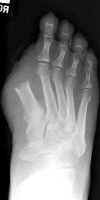

Second toe amputation with resultant hallux valgus

deformity. This is a common complication of second toe amputations and occurs

because the great toe tends to drift toward the third to fill the gap left by the

amputation.